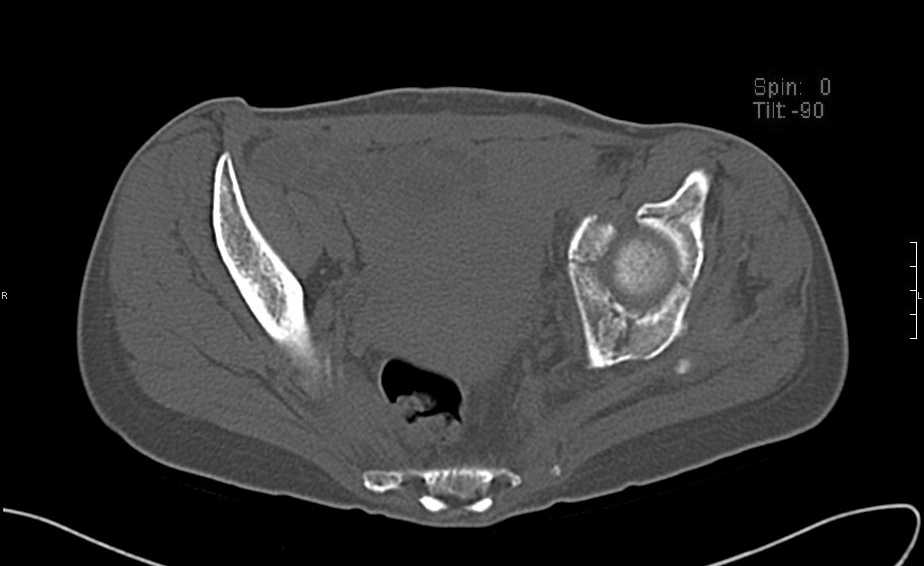

Больная 43 года (промышленный альпинист), 28.07.08 в результате падения с 5 этажа получила политравму:

Перелом свода и основания черепа. Вертикально-нестабильное повреждение таза, осложнённое разрывом мочевого пузыря. Чрезвертельный перелом левого бедра. Перелом правой таранной кости, переломовывих правой кубовидной кости. Тупая травма живота, разрыв печени, ушиб почек. Забрюшинная гематома. В день травмы - лапаротомия, ушивание ран печени. Разрыв мочевого пузыря не диагностирован. Течение болезни осложнилось развитием мочевого затёка и обширной пред- и забрюшинной флегмоны, сформировался свищ мочевого пузыря. 19.8.2008 вскрытие, дренировние флегмоны, ревизия мочевого пузыря, обтурация мочевого свища (свищ закрылся в октябре), 1.10.2008 некрэктомия, пластика по Шеде-Лидскому правой кубовидной кости. По результатам КТ диагностирован рак правой почки (диагностическая находка), 8.10.2008 нефрэктомия справа.

Имеется вертикальное смещение левой половины таза с выраженным отведением крыла (клинически подвижности нет), несросшийся низкий двухколонный перелом левой вертлужной впадины с потерей конгруэнтности, укорочение около5 см, застарелый разрыв лонного сочленения, неправильно сросшиеся переломы обеих ветвей правой лонной кости с укорочением, патологическая подвижность лоно-седалищного фрагмента слева. Правая нижняя конечность неопорна, несмотря на то, что лежа прямую ногу поднимает, ходит на левой ноге (ортопедическая обувь) с костылями, справа тазобедренный ортез. Седалищные нервы работают.Урологи отпустили больную на 6 мес.